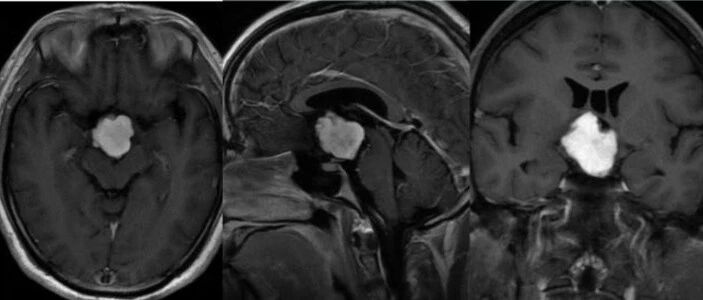

2021年6月,美国泌尿外科学会(AUA)发布了肾脏肿块和局限性肾癌的评估,管理和随访指南,本文为该指南的第2部分,主要内容涉及肾脏肿块和局限性肾癌治疗和随访。